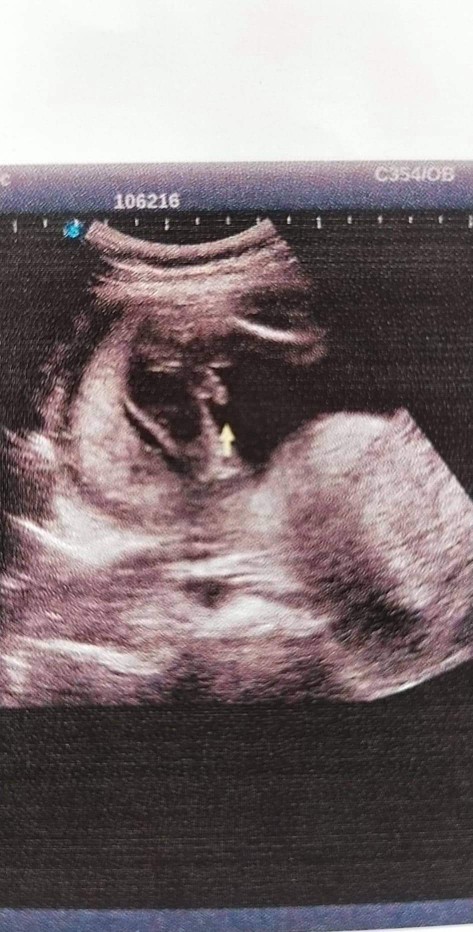

เพศอะไรคะแม่ๆ

แม่ๆช่วยดูหน่อยค่า เพศอะไรเอ่ย

ชายรึป่าวค่ะ

ชายค่ะชัดเจน

ผู้ชายแน่นอน

เพศชายแน่ๆ 100%

จู๋มาเชียว🤭

ผช แน่นอนค่ะ

น่าจะผช.นะคะ

ผู้ชายค่าา🥰

ชายจ้าาา 😁😁